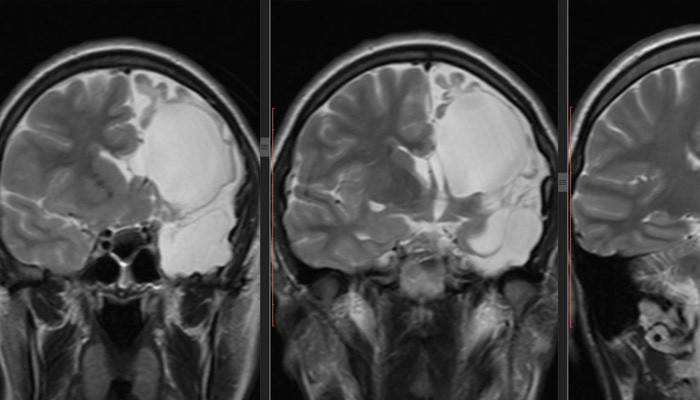

Optimálnou diagnostickou metódou patológie je MRI mozgu. Ak je v konečnom popise výsledkov tomografie cysta, uvedie sa: „arachnoidálne zmeny charakteru mozgomiechového moku.“ Umiestnenie útvaru odhaľuje použitie kontrastných látok. Hlavnou vlastnosťou novotvaru, na rozdiel od nádoru, je schopnosť akumulovať kontrast. Ak je to potrebné, vykonávajú sa laboratórne testy a štúdie: